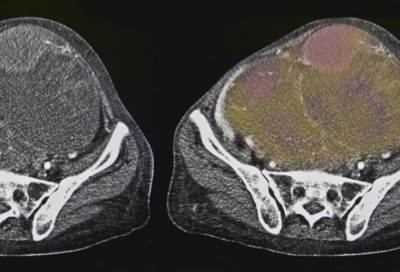

وأضاف العلماء: "لا نعرف السبب الحقيقي وراء هذه الظاهرة، لكن المراقبة السريرية لهؤلاء المرضى أظهرت أن نحو 7.6% ممن أصيبوا بالسكتات الدماغية بدأوا يعانون من السرطان قبل مرور 18 شهرا من إصابتهم بالسكتة، أغلبهم عانى من سرطانات الأمعاء والرئة والبروستات. وبشكل عام، وبعد مرور أكثر من سنة ونصف على الإصابة بالسكتة الدماغية، فإن نحو ثلثي المصابين تتضاعف لديهم احتمالية التعرض للأورام الخبيثة".

ويعتقد العلماء أن الظهور المفاجئ للأورام الخبيثة عند بعض الناس بعد تعرضهم للسكتة الدماغية قد يكون وراءه أن أجسامهم بالأصل كانت مؤهلة للإصابة بالورم، وبعد إصابتهم بالسكتات زادت قابلية ظهور الورم بسبب الخلل الحاصل في دورتهم الدموية، كما أن الحالة النفسية التي يمرون بها بعد السكتة تساهم إلى حد كبير في تطور السرطانات لديهم.